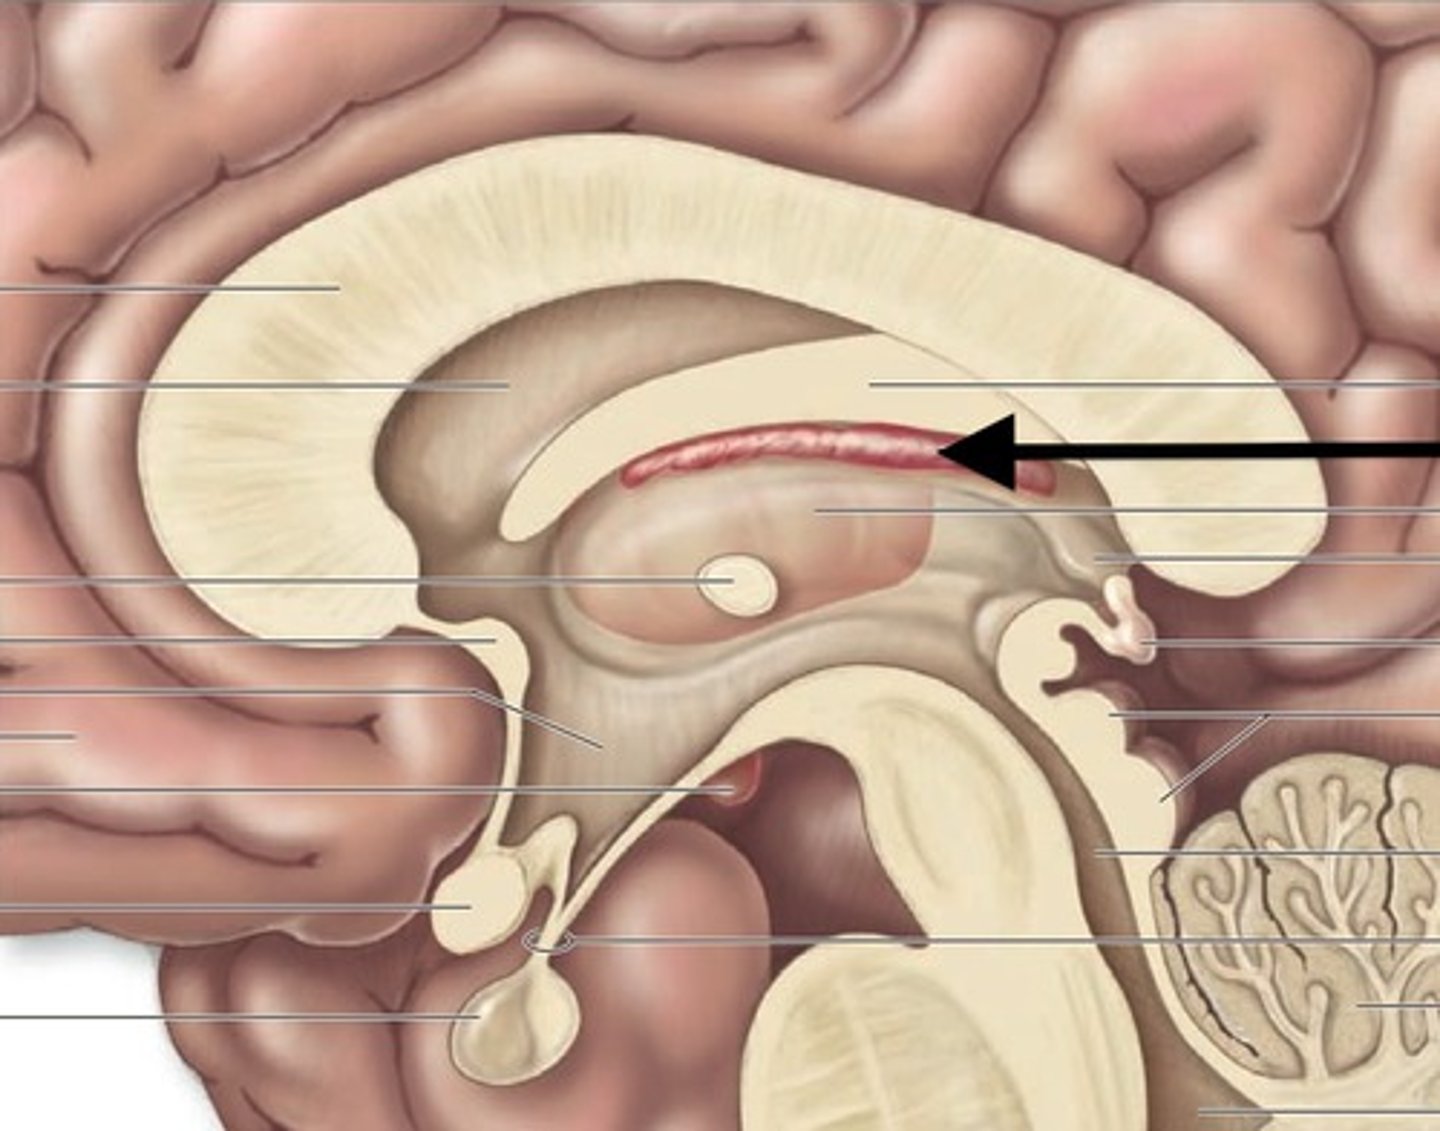

corpus callosum

fornix

choroid plexus (of ventricles)